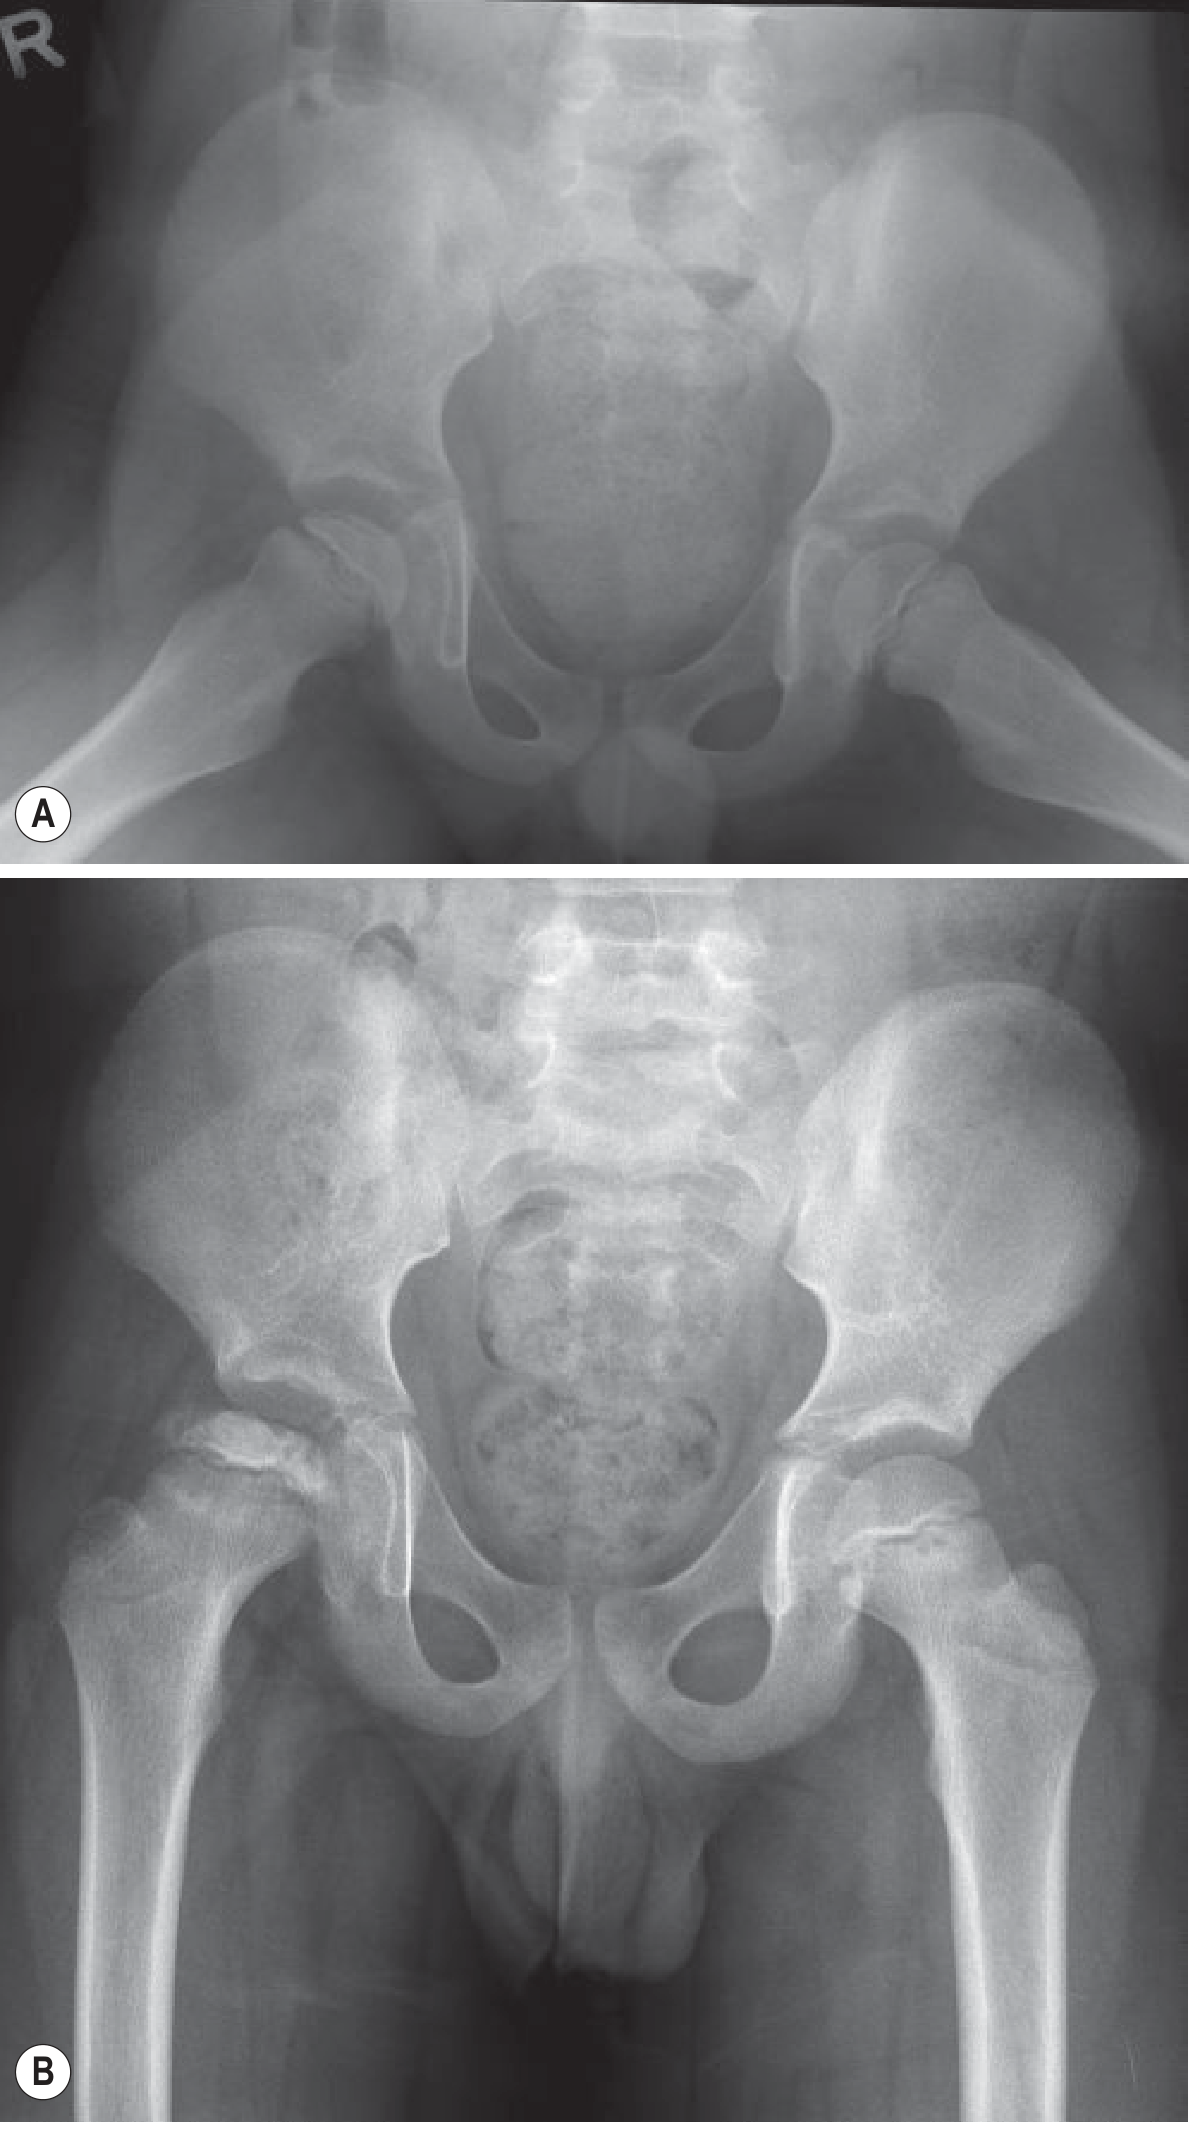

Perthes disease radiographs: (A) Early disease showing subtle right femoral head changes; (B) Advanced disease with marked fragmentation, sclerosis, and deformity of both femoral heads

Fig. — Perthes Disease. (A) Frog lateral at presentation showing the crescent sign (subchondral lucency) of early AVN of the right capital femoral epiphysis. (B) Rapid progression with irregularity, loss of height and sclerosis of the femoral head 8 months later. — Grainger & Allison's Diagnostic Radiology